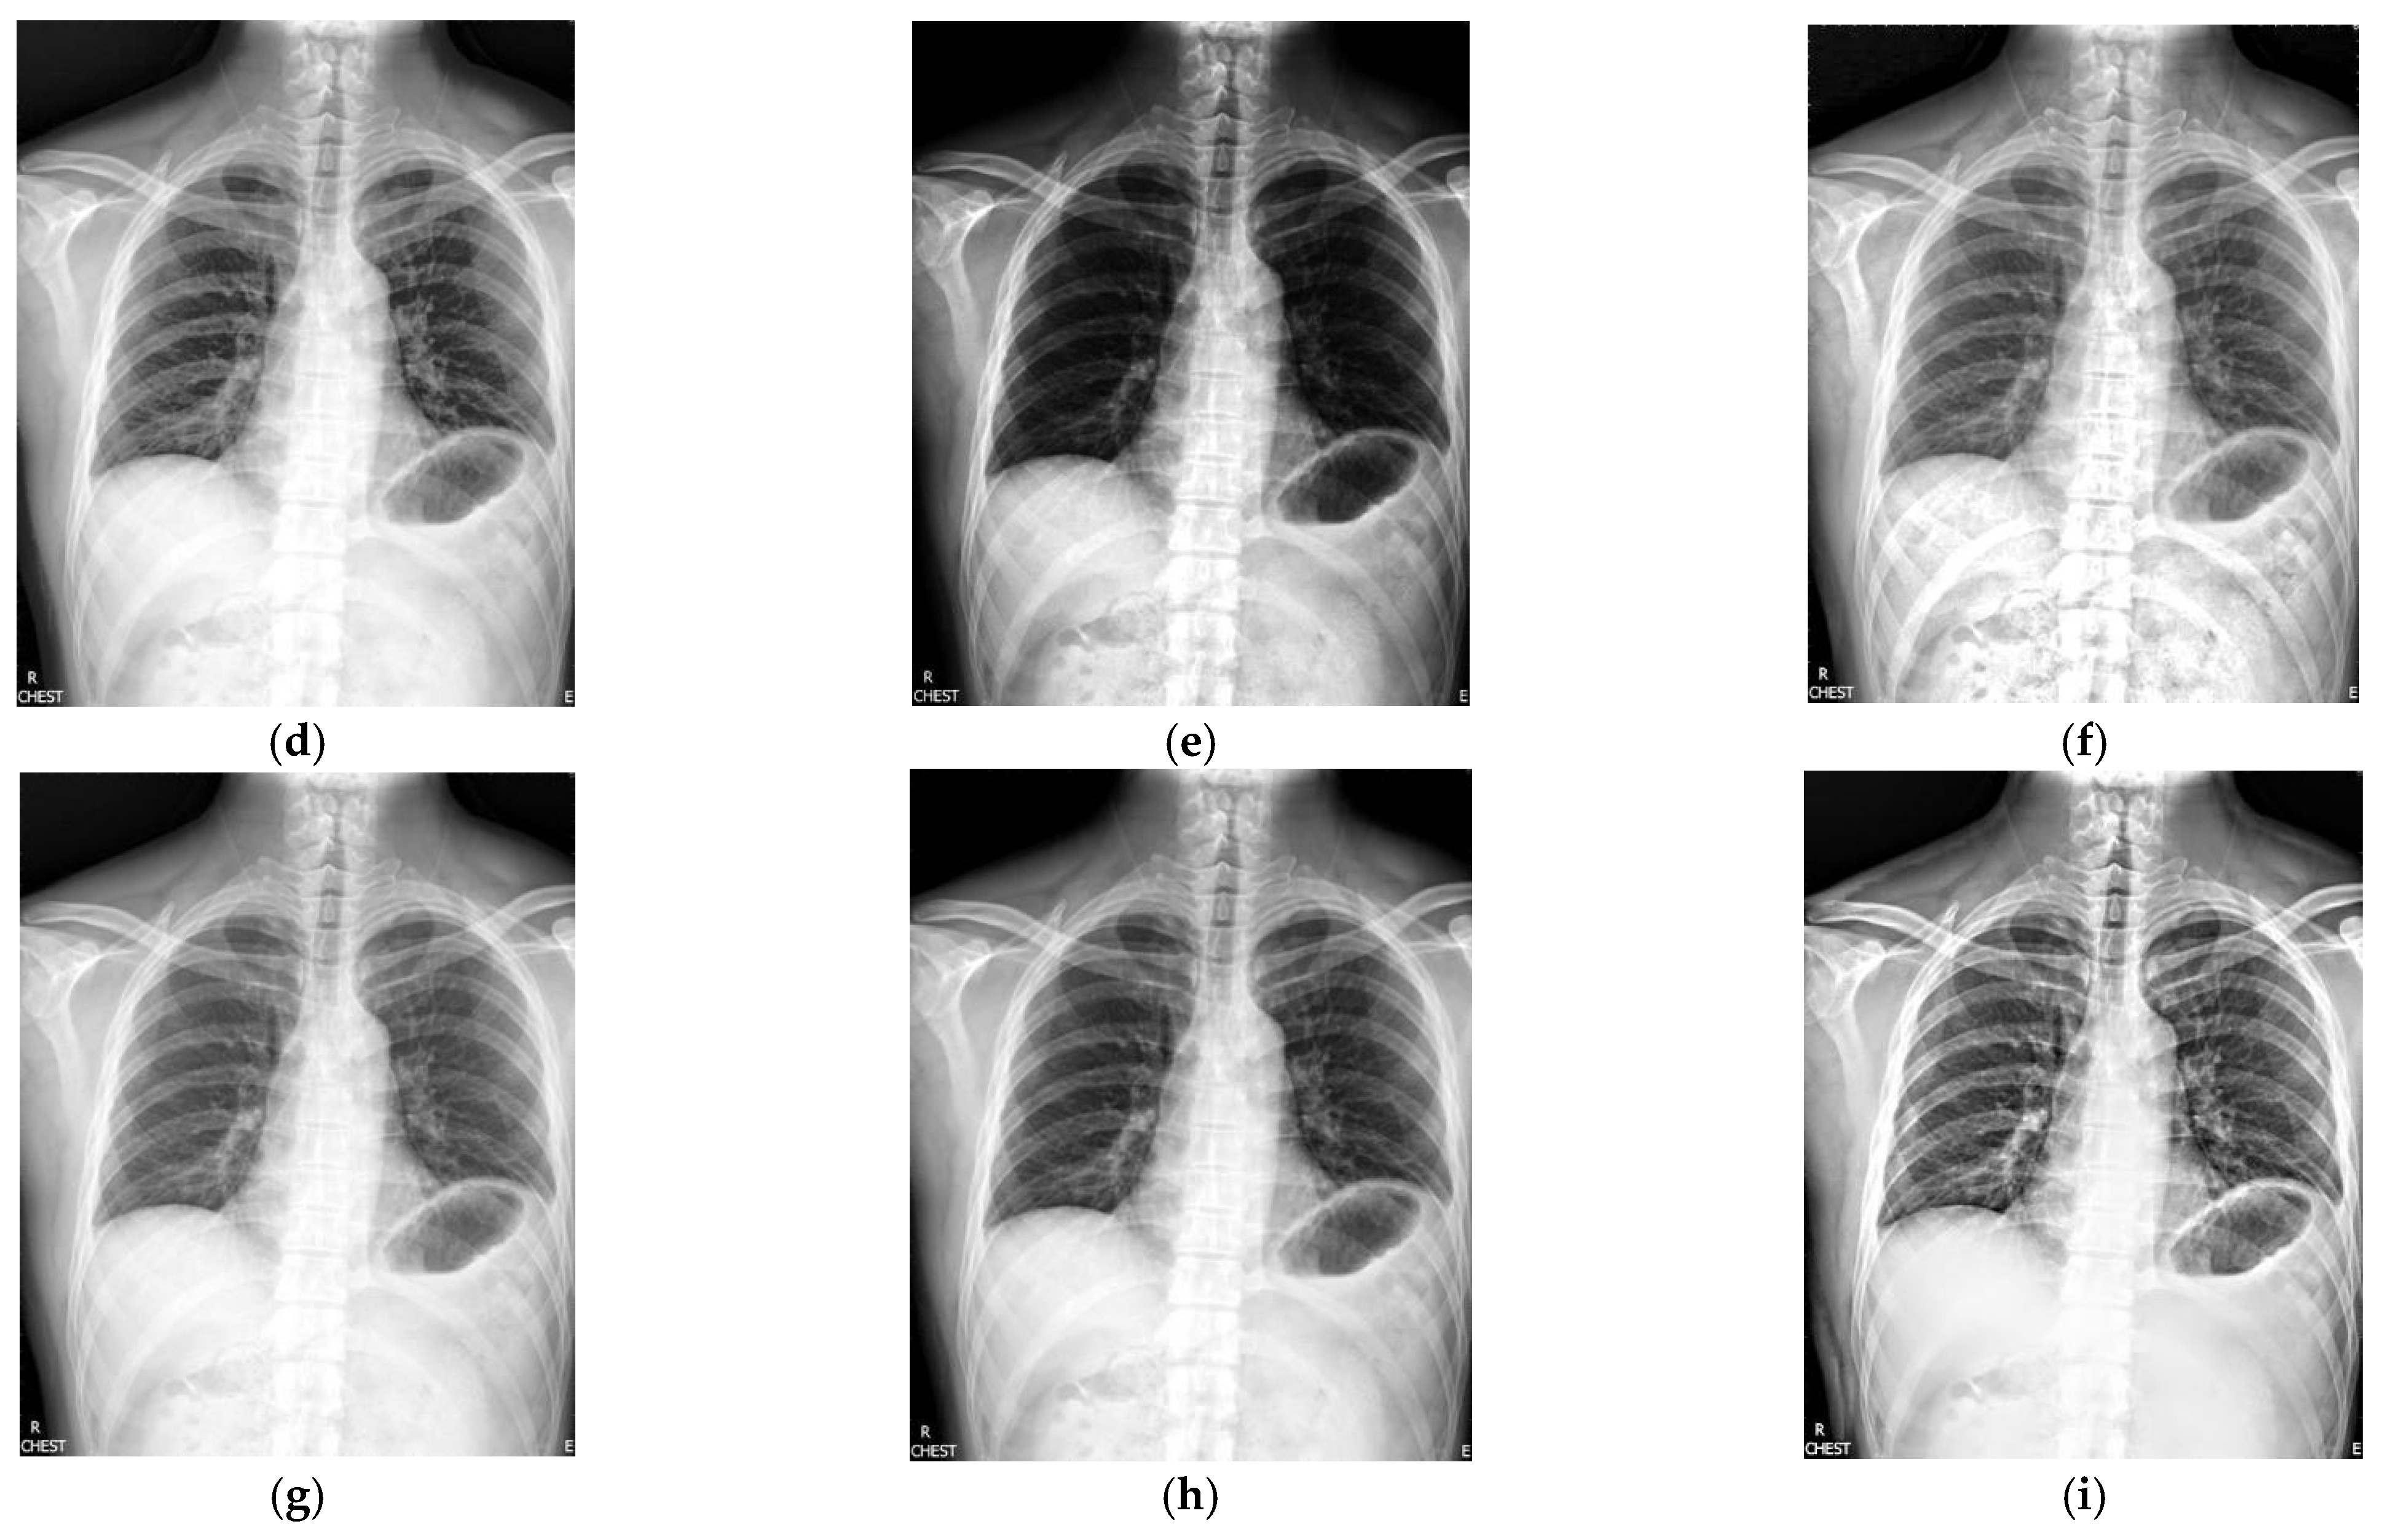

Figure 2 shows the enhancement images of eight approaches experimented on X-ray image 2. Figure 2a shows the original X-ray image 2; Figure 2b is the result obtained by McCann—the contrast is low; Figure 2c presents the image enhanced by RLBHE—it does not achieve the effect of image enhancement, the image is too dark, and we can hardly get effective information from it; Figure 2d shows the result achieved by RESIHE—the effect of enhancement is not obvious; the images obtained by TBCSSR and FuzzyII are shown in Figure 2e and Figure 2h, respectively. The contrast and the definition are low; Figure 2f and Figure 2g show the results enhanced by GDGIF and SMIPC, respectively. The two images appear to have noise amplification. The result enhanced by the proposed algorithm is shown in Figure 2i—it reveals more image details and suppresses the noise. Bone information can be clearly obtained, which is helpful for doctors to diagnose. Table 2 is the evaluation index values of various methods in Figure 2. Except for H, our method is the best for other indicators.

Figure 2.

Comparison on X-ray image 2. (a) Original image; (b) McCann; (c) RLBHE; (d) RESIHE; (e) TBCSSR; (f) GDGIF; (g) SMIPC; (h) FuzzyII; (i) Proposed method.

Table 2.

The metric data of eight methods on X-ray image 2.